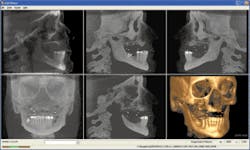

Radiographic study

Following a 20-second scan, the i-CATVision scan data (in DICOM format) was imported into Nobel Biocare Procera software for further 3-D implant planning. Evaluation confirmed the inadequate volume of bone in the maxillary posterior and the need for zygomatic implants. While the thin maxillary anterior alveolar ridge would have been a significant challenge using the free-hand surgical approach, the 3-D images confirmed adequate bone volume for the precision-guided placement of anterior implants. Adequate bone volume was realized in the pterygomaxillary area where additional implants were placed for optimum posterior support. Clear 3-D orientation for the placement of zygomatic implants was reviewed prior to the procedure.